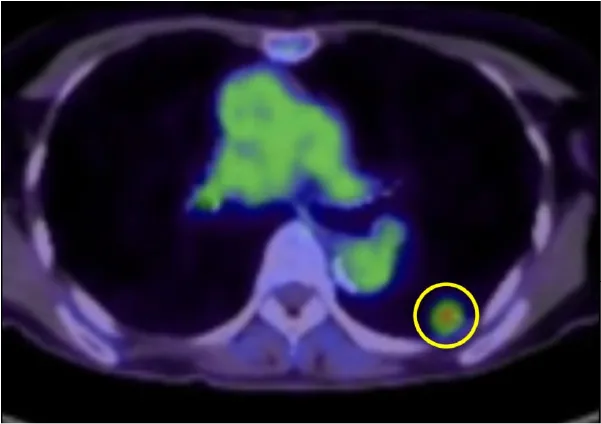

① 肺癌

我が国において、「がん」によって亡くなった人は1981年に脳卒中を抜いて第1位となり、現在、およそ3人に1人は「がん」によって亡くなっています。その中でも肺癌の増加は特に著しく、男性は1993年に胃癌を抜いて第1位に、女性においても大腸癌とともに増加して胃癌を抜いて第2位に、全体においても1998年に胃癌を抜いて第1位となりました。

肺癌の治療については、迅速かつ的確な診断を基に、その肺癌の種類(組織型)や進行度によって適切な治療が必要となります。肺癌の治療には「手術」、「抗癌剤治療」、「放射線療法」と大きく分けて3種類あり、肺癌の種類や進行度によっては、これらの治療を組み合わせた「集学的治療」が必要となります。